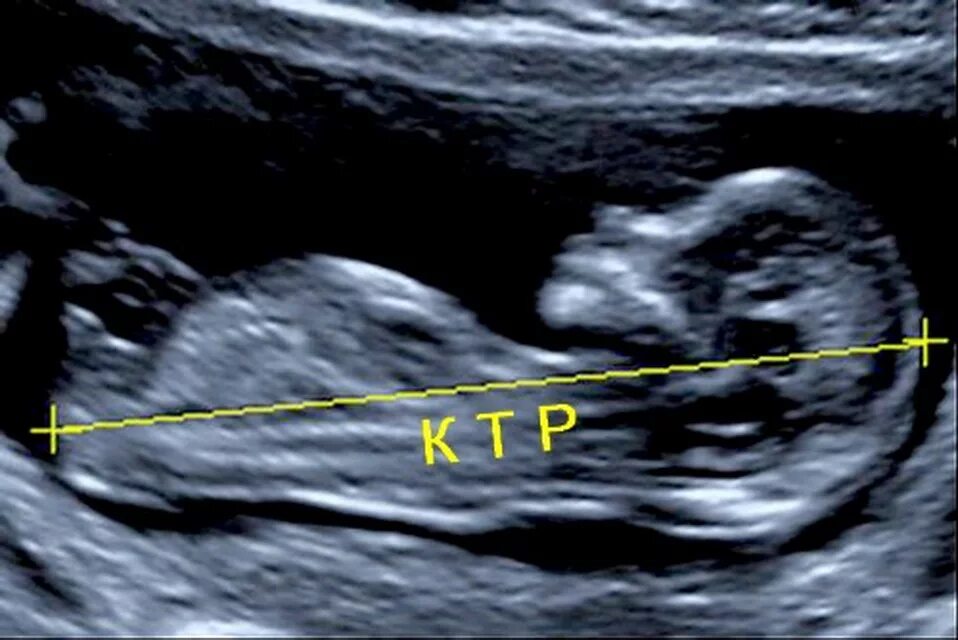

Что такое ктр на узи при беременности